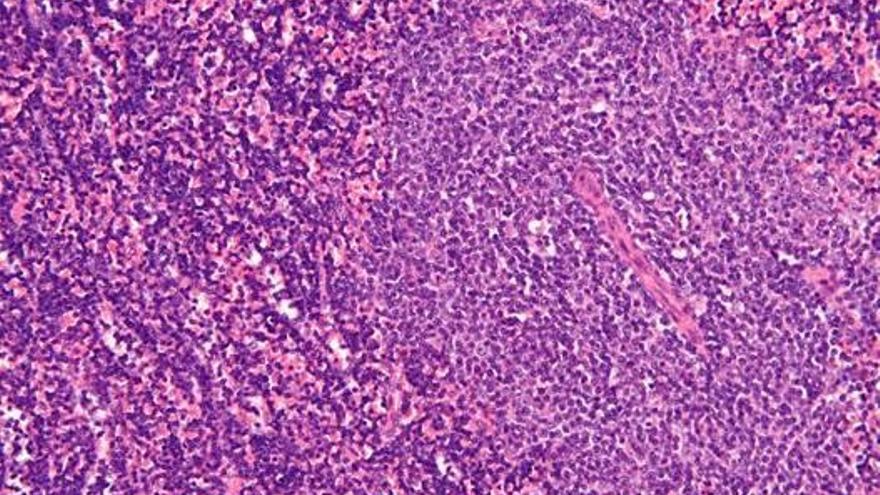

La leucemia linfática crónica (LLC) es un tipo de cáncer de la sangre y es el tipo de leucemia más frecuente en el mundo occidental, con una incidencia en torno a los 5 casos por cada 100.000 habitantes y año.

Se caracteriza por un aumento en el número de linfocitos B, un tipo de glóbulo blanco, que puede detectarse de forma accidental en una analítica rutinaria. En algunos casos puede tener un crecimiento lento y de buen pronóstico, mientras que en otros puede ser rápido y agresivo.